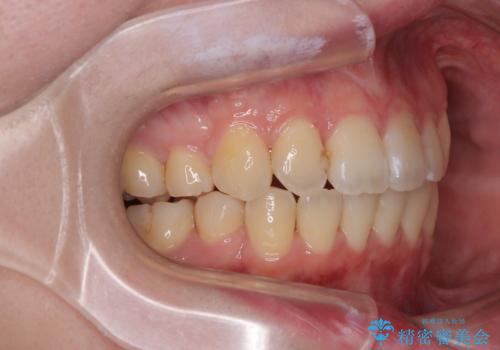

- 上下前歯のデコボコを気にして来院された患者様です。

口元の突出感はあまりなかったものの、デコボコを非抜歯で改善すると出っ歯になる可能性があるため、上下左右の第一小臼歯4本を抜歯し、ワイヤー装置にて矯正治療を行うこととしました。

口元の突出感はなかったものの、捻転や八重歯を改善するために補助装置を併用する必要がありました。

予定の2年半を越えてしまいましたが、無事にきれいな口元に仕上げることができました。